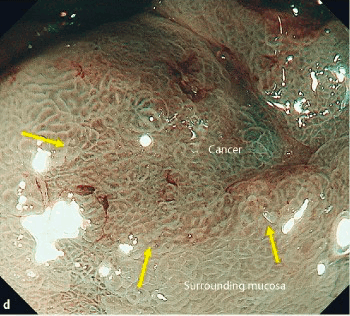

Нерегулярный тип ямочного рисунка; соответствует дисплазии высокой степени или аденокарциноме с поверхностной инвазией.

«Колоноскоп Olympus с изменяющейся жесткостью CF-Q180AL проведен в дистальную треть сигмовидной ободочной кишки, где за изгибом определяется опухолевое образование, экзофитно растущее циркулярно по всем стенкам в просвет кишки и суживающее просвет до 9 мм, проксимальнее сужения колоноскоп провести не представляется возможным. Поверхность опухоли на большем протяжении покрыта грязным налетом фибрина, на остальных участках вишневого цвета, с неровной бугристой поверхностью, при исследовании в режиме NBI определяется нерегулярный и местами разрушенный (VI и Vn) тип структуры ямок эпителия (по классификации S. Kudo) и СР-IIIb тип капиллярного рисунка (по классификации Y.Sano), что соответствует распространенному раку.»